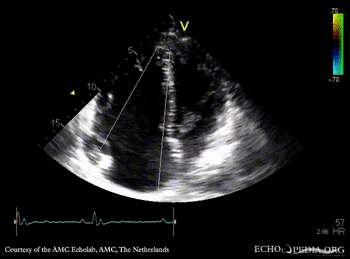

Ebstein anomaly

A4CH: high insertion of tricuspid valve A4CH: Color Doppler, severe tricuspid regurgitation